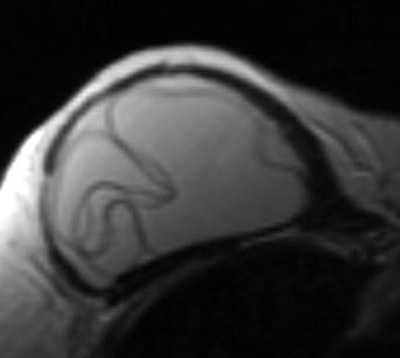

Linguine: After implantation of a silicone or saline breast implant, a fibrous capsule or scar forms around the implant shell. In an intracapsular rupture, the contents of the implant are contained by the fibrous scar, while the shell appears in a group of wavy lines. The linguine sign is most commonly picked up on MRI, and the same findings are seen on CT in patients with bilateral ruptured saline implants.

Breast MRI showing the linguine sign indicating intracapsular implant rupture."It may sound a little silly, but the radiology literature is replete with signs, some more fanciful than others," she concluded, before receiving an enthusiastic round of applause.